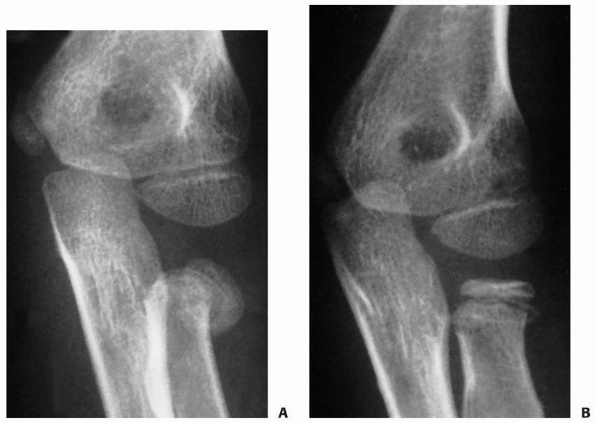

FIGURE 11-11 Valgus (type B) injury. A.

Three weeks after the initial injury, there was evidence of distal migration of this Salter-Harris type IV fracture fragment. Periosteal new bone formation has already developed along the distal metaphyseal fragment (arrow). B. Six months after the initial injury, there is evidence of an osseous bridge formation between the metaphysis and the epiphysis. Subsequently, the patient had secondary degenerative arthritis with loss of elbow motion and forearm rotation. |